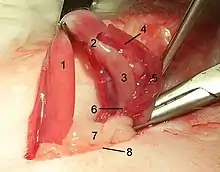

One of the most common elective surgical procedures in animals are those that render animals incapable of reproducing. Neutering in animals describes spaying or castration (also please see castration). To spay (medical term: ovariectomy or ovario-hysterectomy) is to completely remove the ovaries and often the uterus of a female animal. In a dog, this is accomplished through a ventral midline incision into the abdomen. In a cat, this is accomplished either by a ventral midline abdominal incision, or by a flank incision (more common in the UK). With an ovariectomy ligatures are placed on the blood vessels above and below the ovary and the organ is removed. With an ovariohysterectomy, the ligaments of the uterus and ovaries are broken down and the blood vessels are ligated and both organs are removed. The body wall, subcutis, and skin are sutured. To castrate (medical term: orchiectomy) is to remove the testicles of a male animal. Different techniques are used depending on the type of animal, including ligation of the spermatic cord with suture material, placing a rubber band around the cord to restrict blood flow to the testes, or crushing the cord with a specialized instrument like the Burdizzo.